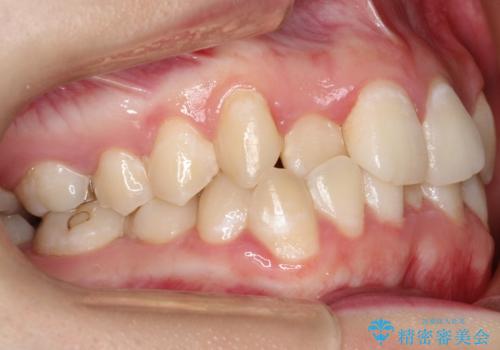

前歯が前後反対にかんでいる インビザラインによる矯正

- 前歯のがたつきを気にされて来院されました。

上顎の前から二番目の歯が内側に入り込んでおり、前後反対にかんでいる状態でした。

しっかりとマウスピースを使用していただけたので、順調に治療を終えることができました。